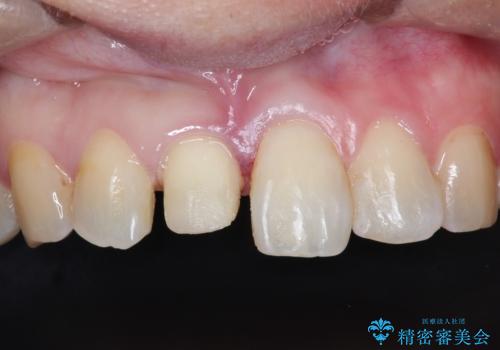

インビザラインによる矯正治療で前歯の歯並びを改善し、セラミッククラウン装着により歯の形態の回復をする計画としました。

矯正とセラミックを併用することで、より完成度の高い状態に仕上げることができました。